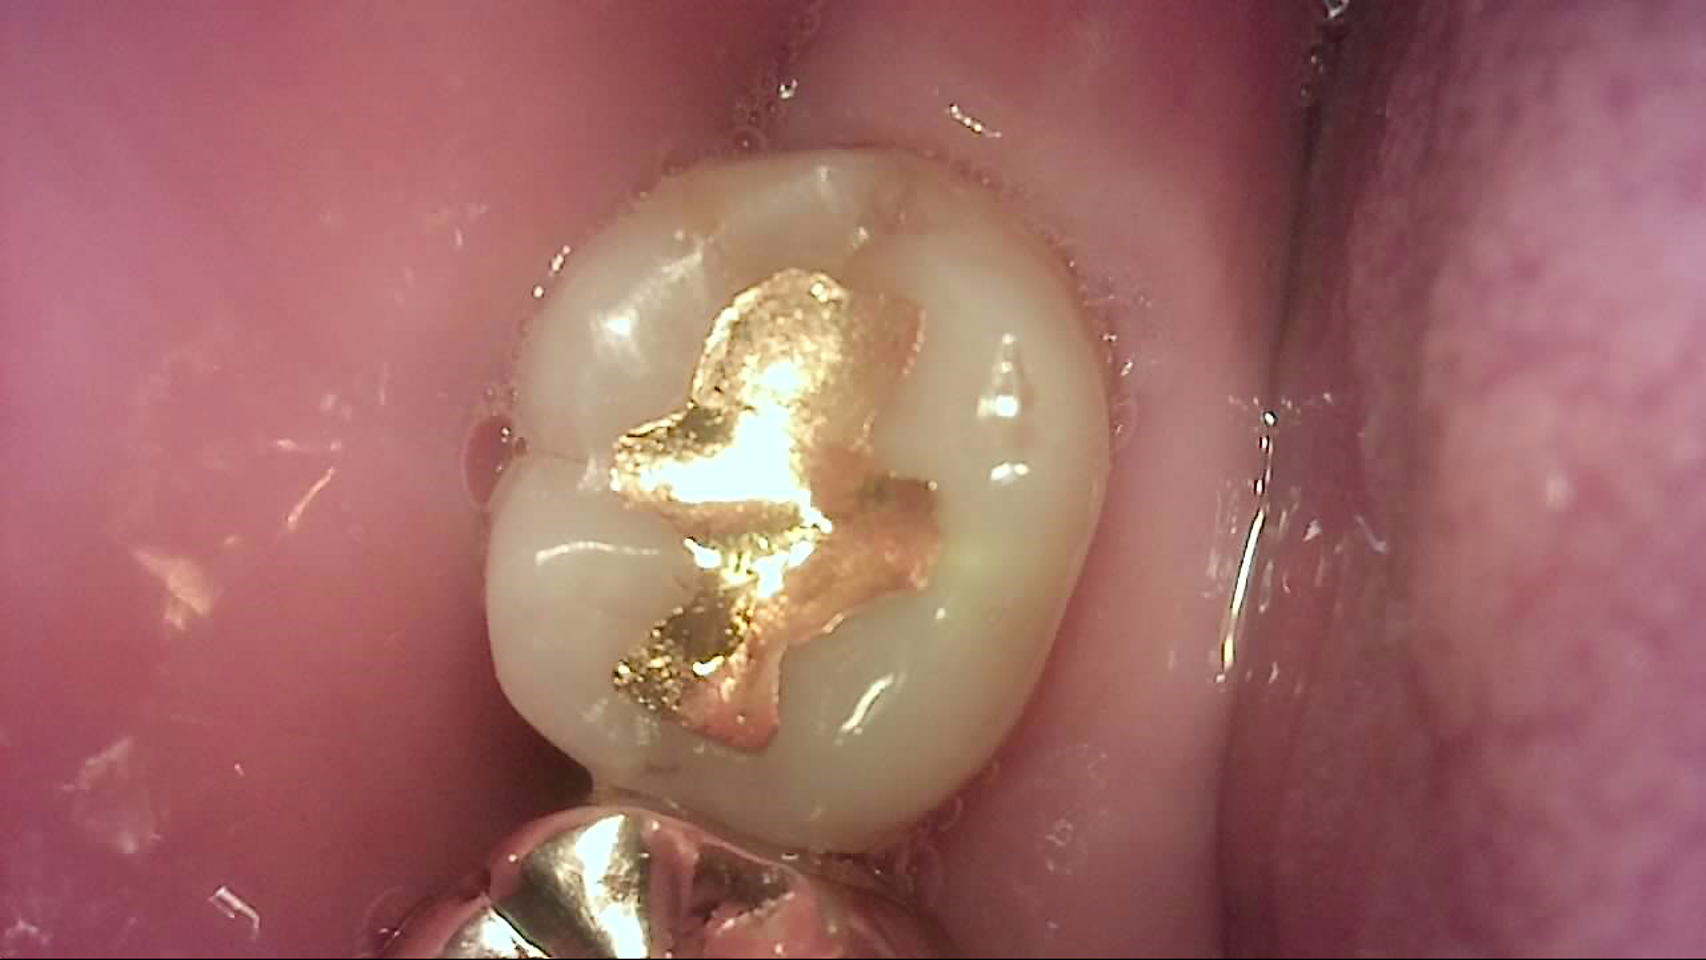

Crack

큐레이캠프로, 큐레이펜씨